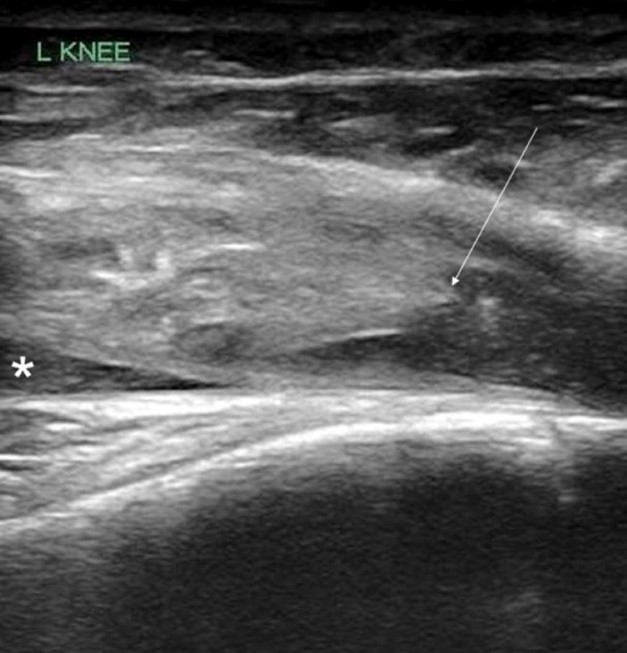

POCUS of the left knee was performed, which was concerning for a patellar tendon rupture and a joint effusion. (Figure 1 and Video 1) In addition, there was posterior acoustic shadowing obscuring part of the patellar tendon concerning for an avulsed bony fragment. (Figure 2) X-rays were performed, which confirmed the suspected diagnosis of a left tibial tubercle avulsion. (Figure 3) The patient was ultimately taken to the operating room for an Open Reduction and Internal Fixation (ORIF) by Orthopedic Surgery and discharged home the following day in a knee brace.

Figure 1. Ruptured patellar tendon (arrow) with joint effusion (*) seen in longitudinal view

In our case report, we successfully identified key features suggestive of tibial tubercle fractures: disruption of the patellar tendon, posterior acoustic shadowing of a bone fragment, and a large joint effusion. To perform knee ultrasound, the linear probe should be used and placed inferior to the patella in sagittal plane. The patellar tendon should be visualized in two planes, fanning through it completely (Video 1), and compared to the contralateral normal knee. (Figure 4) Abnormal findings suggestive of epiphyseal fractures include disruption of the tendon, an increased hypoechoic space adjacent to or posterior to the tendon (suggestive of either hemarthrosis or a hematoma), or a hypoechoic zone (ie, posterior acoustic shadowing due to an avulsed bony fragment).3,4